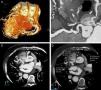

Se realizó una tomografía computarizada cardiaca (TCc) que mostró situs inversus con coronaria derecha (CD) de origen normal y trayecto ectásico con placas fibrocalcificadas sin estenosis luminal significativa. Sin embargo, el árbol coronario izquierdo (ACI) se originaba en la arteria pulmonar (AP), presentado una amplia red de colaterales entre ambos sistemas (fig. 1). El análisis de densidad (fig. 1D) sugería la existencia de un cortocircuito izquierda-derecha con flujo desde CD a ACI.

A: reconstrucción volumétrica en la que se observa la CD de gran tamaño con una amplia red de colaterales que van hacia el árbol coronario izquierdo. B y C: reconstrucción multiplanar (B) y corte axial (C) en las que se observa la CD con origen normal y el Tronco Común Izquierdo originado en la Arteria Pulmonar. D: análisis del grado de atenuación en Unidades Hounsfield en el lumen de la Arteria Pulmonar, la Aorta y el Tronco Coronario Izquierdo. Obsérvese que las mediciones en la AO y en el ACI son prácticamente similares, lo cual sugiere la existencia de un cortocircuito izquierda-derecha.

ACI: árbol coronario izquierdo; AO: aorta; AP: arteria pulmonar; CD: coronaria derecha.